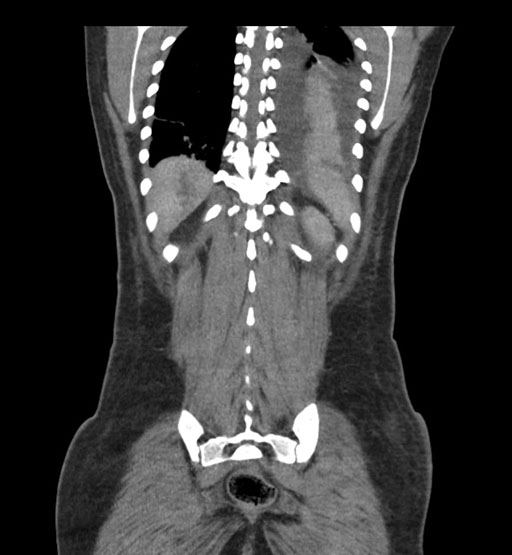

Coronal Arterial

Coronal Venous